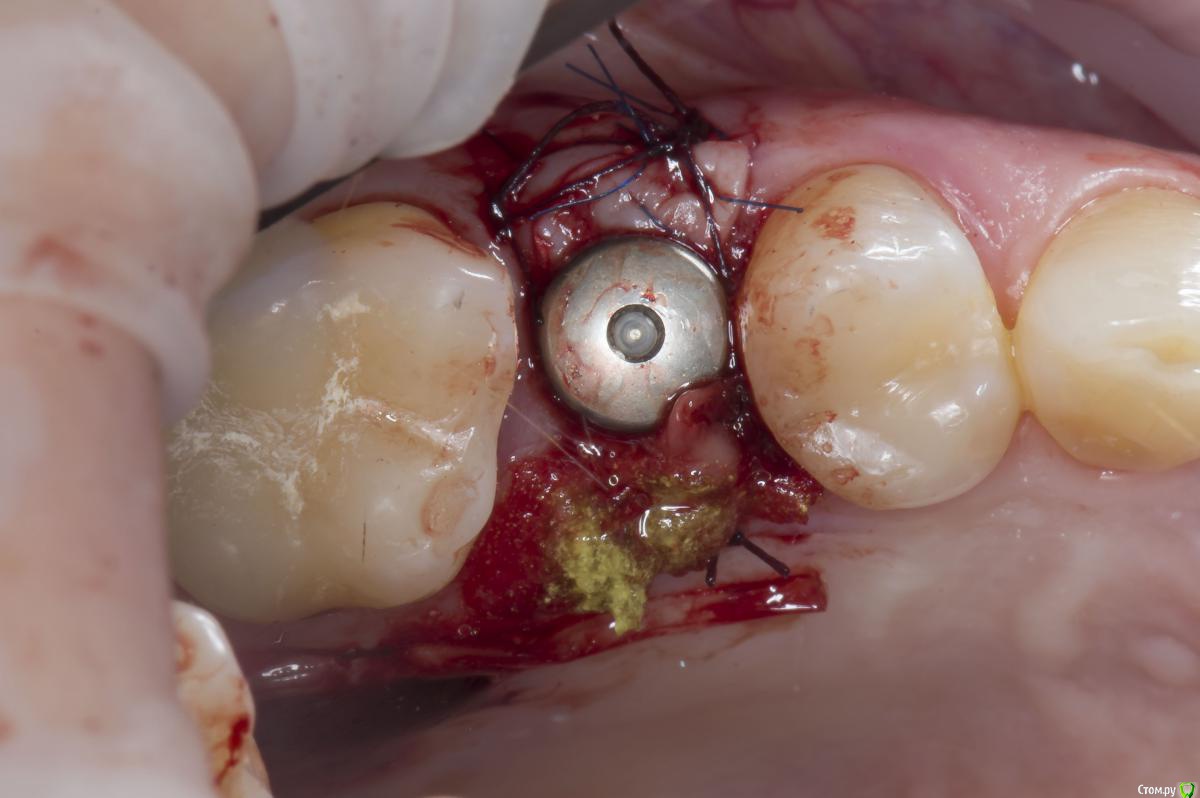

Sampson Опубликовано 10 августа, 2018 Поделиться Опубликовано 10 августа, 2018 (изменено) Очень мило для первого раза.. Здравствуйте коллеги.Сегодня поставил первый свой одномоментныйИзначальная картинаУдалениеСверление и контрольГрафтБолтКТФдмP.S. еще сдт взял с неба и вестибулярно подшил. А с неба заложил prf. Изменено 10 августа, 2018 пользователем Sampson 7 Ссылка на комментарий

Aquarius Опубликовано 10 августа, 2018 Поделиться Опубликовано 10 августа, 2018 Хорошая работа. Только куда графт делся после 3D заполнения? Отсосом забрали? витки импланта видны в лунке, а на предыдущем фото графт есть 1 Ссылка на комментарий

Sampson Опубликовано 10 августа, 2018 Автор Поделиться Опубликовано 10 августа, 2018 (изменено) Хорошая работа. Только куда графт делся после 3D заполнения? Отсосом забрали? витки импланта видны в лунке, а на предыдущем фото графт естья думал с неба он не обязателен:-) Просто ставиш имплан на уровне кости и все;-) Но спасибо учту. Изменено 10 августа, 2018 пользователем Sampson Ссылка на комментарий

Карен Аванесов Опубликовано 10 августа, 2018 Поделиться Опубликовано 10 августа, 2018 Молодец! Не загордись теперь)))) так теперь критика: болт.... забить болт.... ну вы поняли)) 1 Ссылка на комментарий

Evikrol Опубликовано 11 августа, 2018 Поделиться Опубликовано 11 августа, 2018 Отлично, только шахта выходит на вестибулярный бугор, не отдавай ортопеду который любит винтовую. Ссылка на комментарий